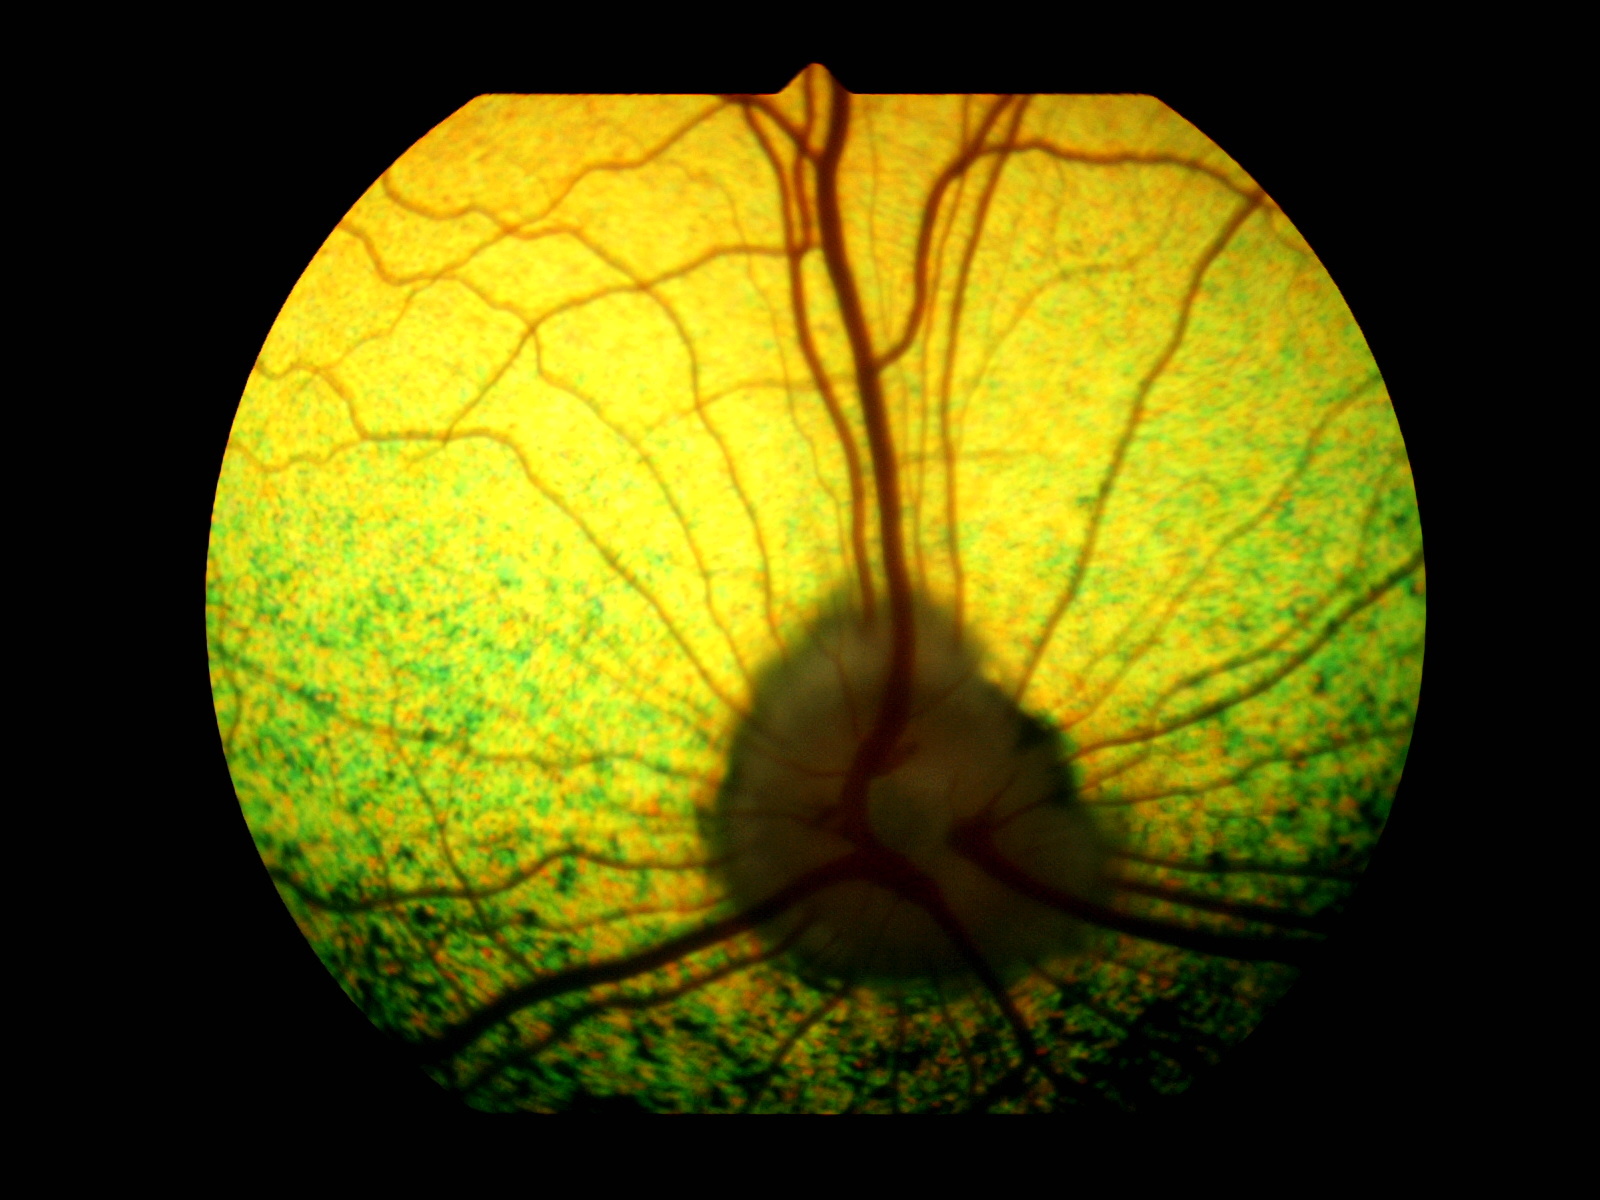

Bei der klassischen PRA beginnen die „Stäbchen“ die für das Nachtsehen zuständig zuerst zu degenerieren bzw. abzusterben. Dieser Vorgang ist nicht schmerzhaft. Im Anfangsstadium ist auffällig, dass sich die Tiere im Dämmerlicht oder im Dunkeln unsicher bewegen, ängstlich sind und unbekannte Objekte oder Personen verbellen. Teilweise stoßen die Tiere auch gegen ihnen unbekannte Dinge an oder weichen dem Besitzer nicht mehr von der Seite. Ein weiteres Zeichen ist der unvollständige Schluss der Pupillen bei einfallendem Licht und ein stärkeres “Leuchten” der Augen in der Dunkelheit als gewöhnlich, was ein Zeichen für eine dünner werdende Netzhaut ist. Dadurch kommt die unter der Netzhaut gelegene Schicht, das leuchtende Tapetum lucidum, verstärkt zum Vorschein. Diese Symptome verschlechtern sich dann in den darauffolgenden Monaten bis Jahren und führen zu einer spürbaren Sehverschlechterung auch im hellen Licht, da dann auch die „Zapfen“ beginnen zu degenerieren. Auch dieser Vorgang ist nicht schmerzhaft. Zwischen den ersten Symptomen und der vollständigen Erblindung vergehen in der Regel 3-6 Jahre.  Selten gibt es PRA Formen, bei welchen zuerst die Zapfen und im Anschluss daran die Stäbchen degenerieren. Dann tritt genau der umgekehrte Fall ein und die Tiere erblinden zuerst bei hellem Licht und anschließend auch bei Dunkelheit, dies sind Sonderformen und enden leider auch immer mit der vollständigen Erblindung des Tieres. Eine häufige Folgeerkrankung der PRA stellt der graue Star (Katarakt oder Eintrübung der Linse) dar. Als Folge des grauen Stars kann nach einigen Jahren der grüne Star (Erhöhung des Augeninnendrucks) auftreten. Der grüne Star gehört mit zu den schmerzhaftesten Erkrankungen des Auges und kann zum Verlust des gesamten Augapfels führen. Aus diesem Grunde sollten Tiere, die an der PRA erkranken, ca. einmal jährlich zu einer Kontrolluntersuchung der Augen vorgestellt werden, damit weitere Folgeschäden frühzeitig erkannt und dann behandelt werden können, um schmerzhafte Zustände zu vermeiden.

Ein auf Augenerkrankungen spezialisierter Tierarzt (Veterinär-Ophthalmologe) kann die Diagnose PRA anhand der typischen Symptome und der Befunde stellen, sobald die Erkrankung klinisch ausgebrochen ist, d.h. sobald auch nur geringe Anzeichen einer Sehschwäche auffällig werden. In Einzelfällen, in denen z.B. der graue Star die Sicht auf die Netzhaut verhindert, kann die Diagnose auch mit Hilfe eines Elektroretinogrammes (ERG) gestellt werden. Das ERG ist eine Untersuchung der Netzhautfunktionen, die mit einem EKG (Elektrokardiogramm) des Herzens verglichen werden kann.